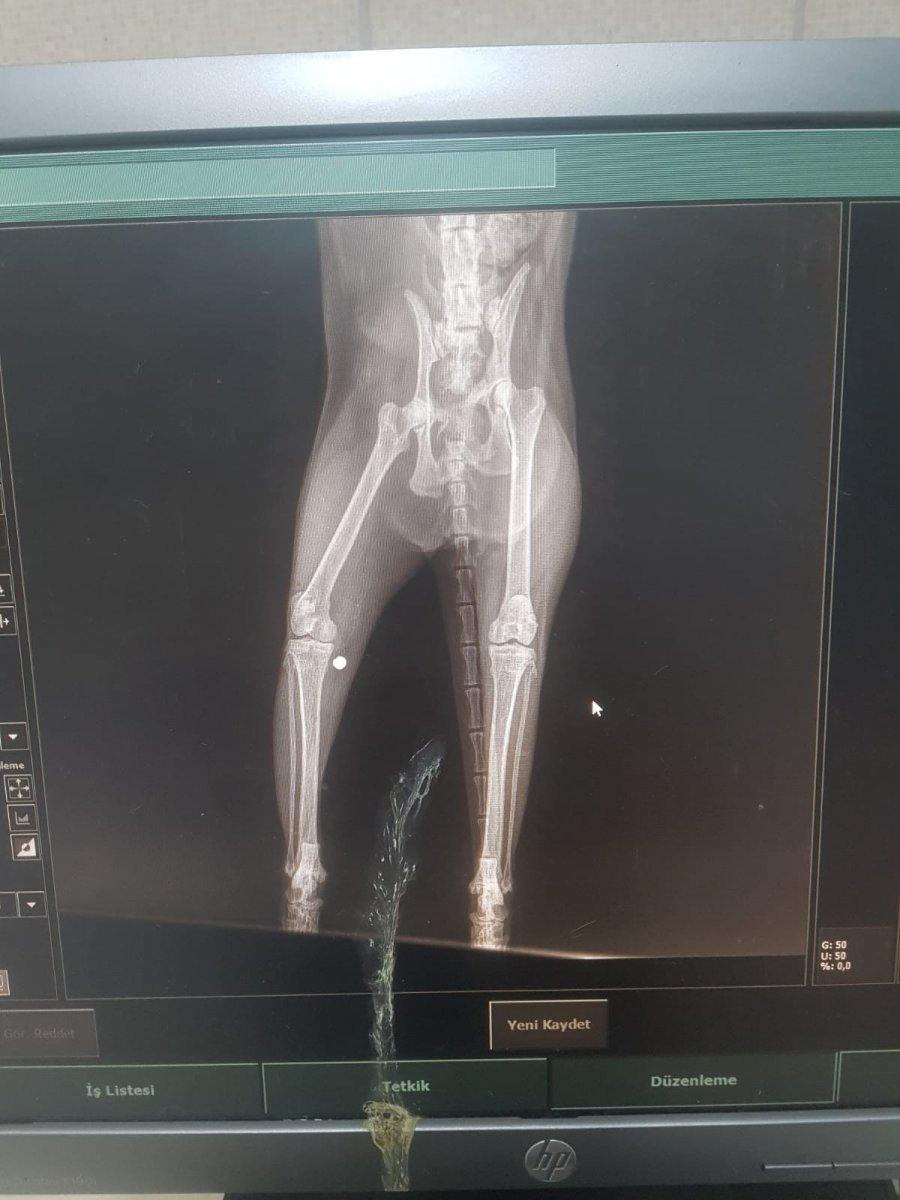

Yapılan detaylı incelemelerin ardından röntgen çeken ekipler, büyük bir şok yaşadı. Sinir bölgesine kurşun isabet ettiği görülen kedi hemen ameliyata alındı.

VÜCUDUNDAN KURŞUN ÇIKTI

Veterinerlerin yaptığı başarılı ameliyatla kurşun kedinin vücudundan çıkarıldı. Kedinin vücudundan çıkarılan kurşun hayrete düşürürken, kurşunun acısıyla bitkin düşen kedi de ameliyatla birlikte rahatladı.